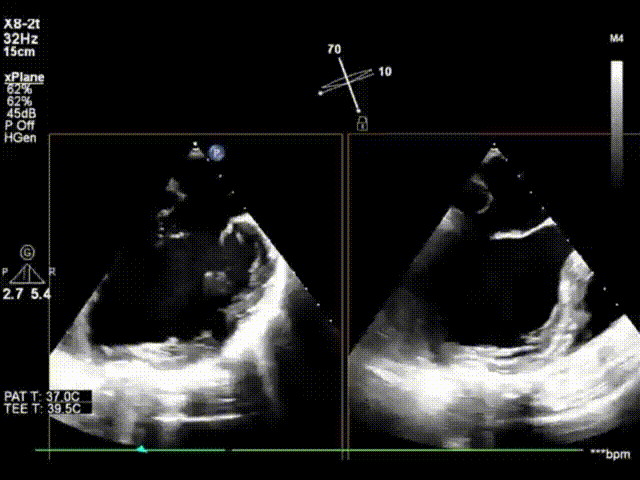

术前心超显示大量二尖瓣反流(反流宽度约1.8cm)

X-plane模式外科视角下,跨瓣器顺利跨瓣,第一个ValveClamp夹合器上下夹定位夹合